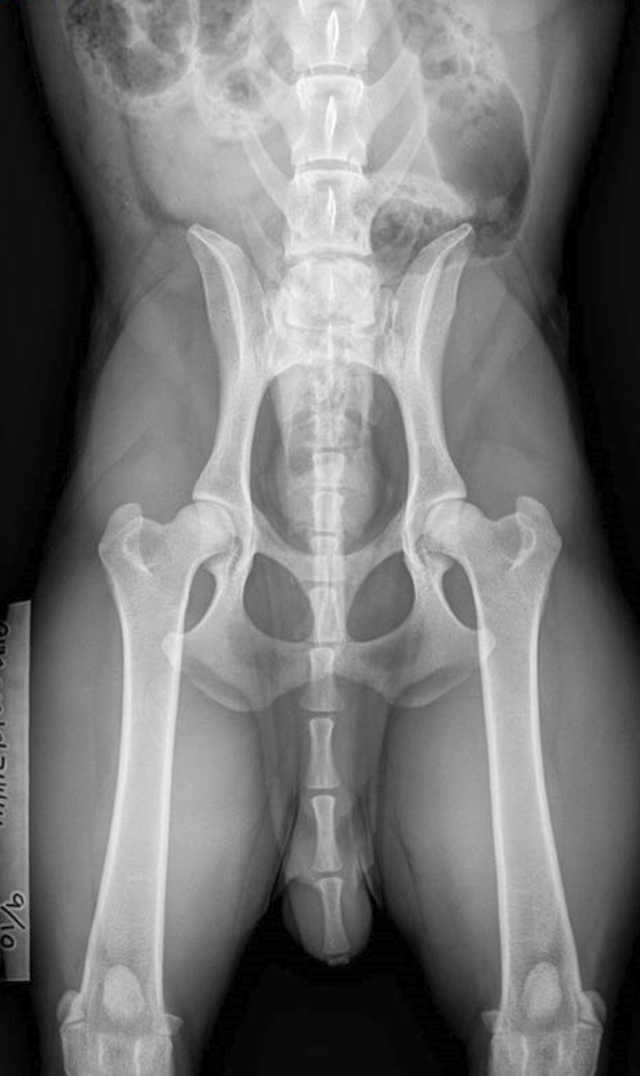

Höftledsdysplasi, HD

HD är en felaktig utveckling av höftleden och en relativt vanlig skelettrubbning hos många hundraser, så även Breton.

Rubbningen i ledens utveckling äger rum under hundens uppväxttid. Först när skelettet vuxit färdigt kan man bedöma höftledernas utseende med hjälp av röntgen.

För officiell röntgen gäller att bretonen är minst 12 månader gammal.

Gradering av höftledsstatus

Gradering av höftledsstatus sker enligt normer fastställda av Fédération Cynologique Internationale, FCI. Normerna bygger på dels passform mellan höftledskula och höftledsskål, dels på djupet av skålen dvs. hur djupt höftledskulan ligger inne i skålen. Lederna graderas i 5 grupper:

A – normala höftleder grad A

B – normala höftleder grad B

C – lindrig dysplasi

D – måttlig dysplasi

E – höggradig dysplasi